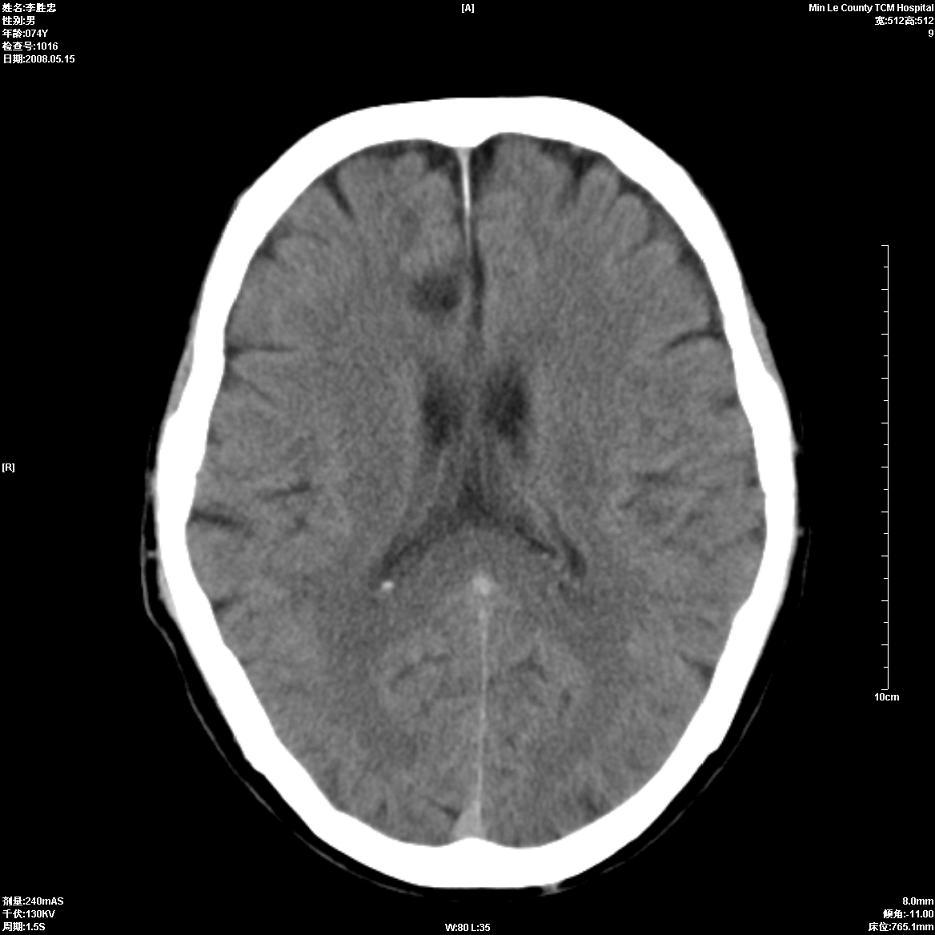

以下是引用hhcckk在2008-5-30 14:26:00的发言:[br]病灶跨中线,有占位效应,强化不明显,考虑胼胝体区低级别的星形细胞瘤可能性大,建议mr检查